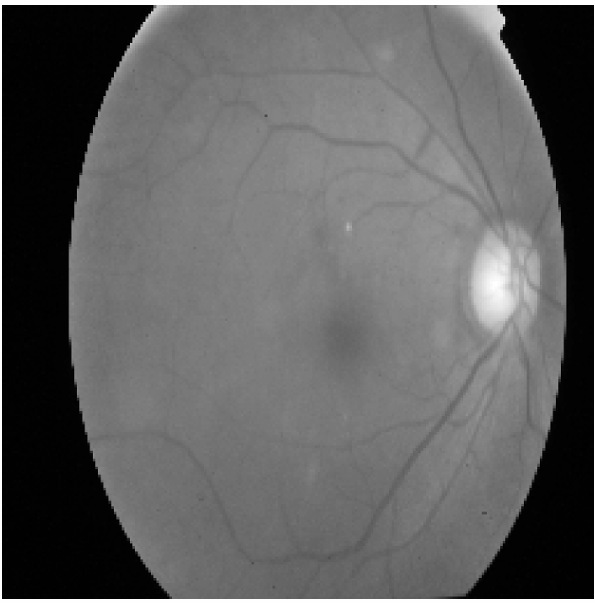

Figure 1: Illustration of the preprocessing pipeline applied to a fundus image. From left to right: (a) Original color image, (b) grayscale conversion used for HOG computation, and (c) corresponding Histogram of Oriented Gradients (HOG) visualization highlighting edge and texture features.